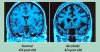

Мы и так с возрастом регрессируем, память ухудшается, здоровье шалит....а, если ещё помогать алкоголем, то мозги все сливаются в унитаз в прямом смысле этого слова. Мозг - такой же орган, как и мышцы, и его тоже надо "качать", а точнее информацию закачивать, она ему необходима. Если человека положить и не дать шевелиться - что будет с мышцами??? АТРОФИЯ.

Так же и с мозгом - не давая пищи для ума, не заставляя решать новые задачи, у него тоже наступает АТРОФИЯ....